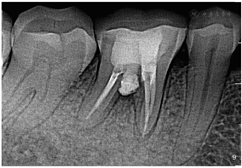

面呈开髓洞型,髓腔暴露,探及远中髓室底穿孔区(图1),面积约为4mm×3mm,穿髓孔区域探痛(+),叩(+),冷热刺激无反应,未探及牙周袋,患牙无松动。根尖片示:46

面可见低密度缺损影像,远中髓室底区域穿孔,大约4 mm×3mm,并伴有近中根管口的破坏,根尖区可见边界不清的低密度暗影(图2)。